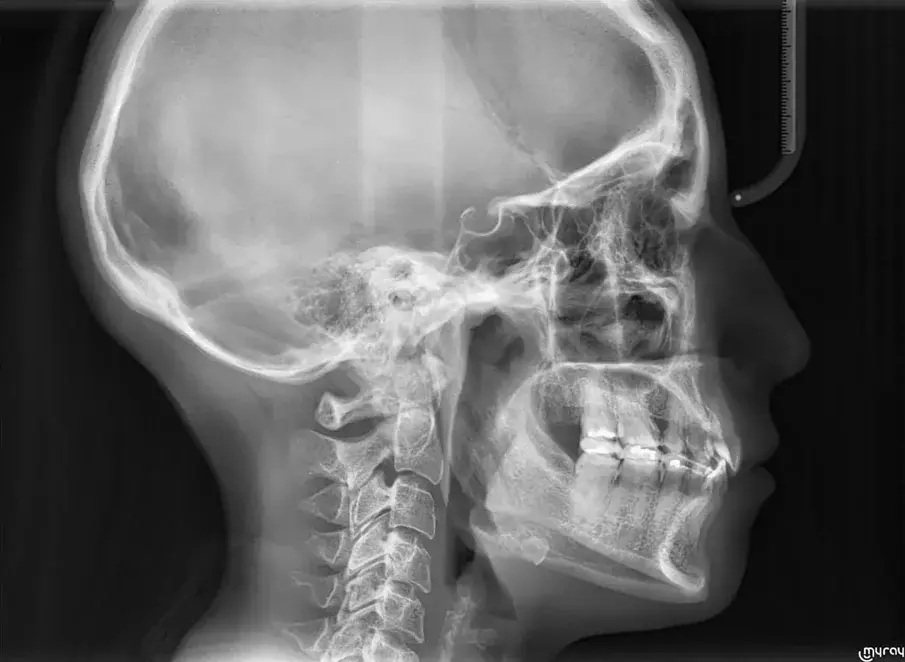

Фиг. 4а.

Първоначална цефалометрична рентгенография и панорамна дентална томография.

Фиг. 4b.

35-годишна пациентка постъпва със струпване на зъби, болки в мускулите и ставите и главоболие след събуждане. При прегледа се установява I скелетен клас със струпване и бимаксиларна протрузия. Изследването на лицето показа конвексен профил с изпъкнали устни и квадратна форма на лицето, която се засилва при усмивка (фиг. 1-4). Тя съобщава за бруксизъм и се наблюдава двустранна хипертрофия на масетерите, но няма изменения в темпоромандибуларните стави.